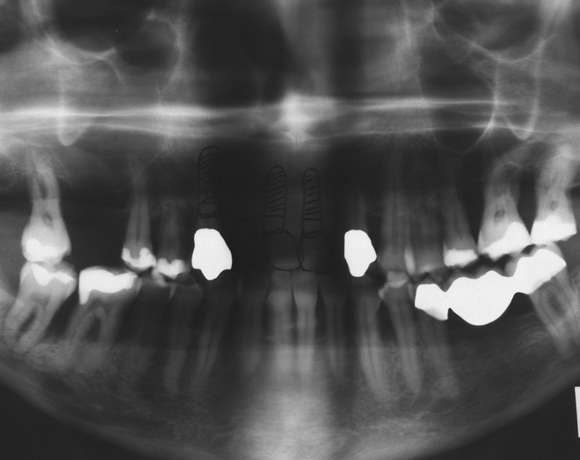

Bei dieser Patientin waren die Zähne 16, 12, 11 und 21 mit einer Modellgußprothese versorgt.

Der Zahn 13 war aus parodontalen Gründen stark gelockert und sollte extrahiert werden.

Als Ersatz wurden drei Implantate für die Zähne 13, 11, 21 gesetzt, die Lücke 15 – 17 mit einer

vollkeramischen Brücke versorgt. da die Patientin eine metallfreie Versorgung wünschte,

wurden Zeramex C Implantate gewählt, auch der Zahn 22 wurde mit einer vollkeramischen

Krone versorgt.